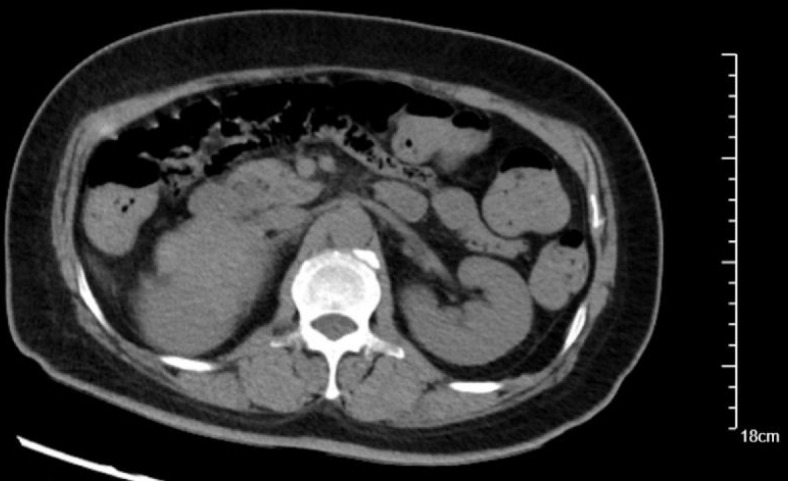

Case summary: A 53-year-old female presented predominantly with persistent and refractory vomiting as her chief complaint, accompanied by signs of acute heart failure [left ventricular ejection fraction (LVEF) 30%]. Initial evaluation at a primary hospital, including coronary angiography (revealing only mild stenosis), led to a misdiagnosis of coronary artery disease. Despite standard anti-thrombotic, anti-heart failure, and anti-emetic therapy, her vomiting persisted and heart failure did not resolve. Subsequent hospitalization revealed dramatic paroxysmal hypertension (202/129 mmHg to 97/51 mmHg) and fever. Significantly elevated plasma metanephrines and normetanephrine, combined with abdominal computed tomography and magnetic resonance imaging, confirmed a right adrenal pheochromocytoma. This diagnosis was significantly delayed due to the atypical prominence of gastrointestinal symptoms masking the underlying endocrine crisis.